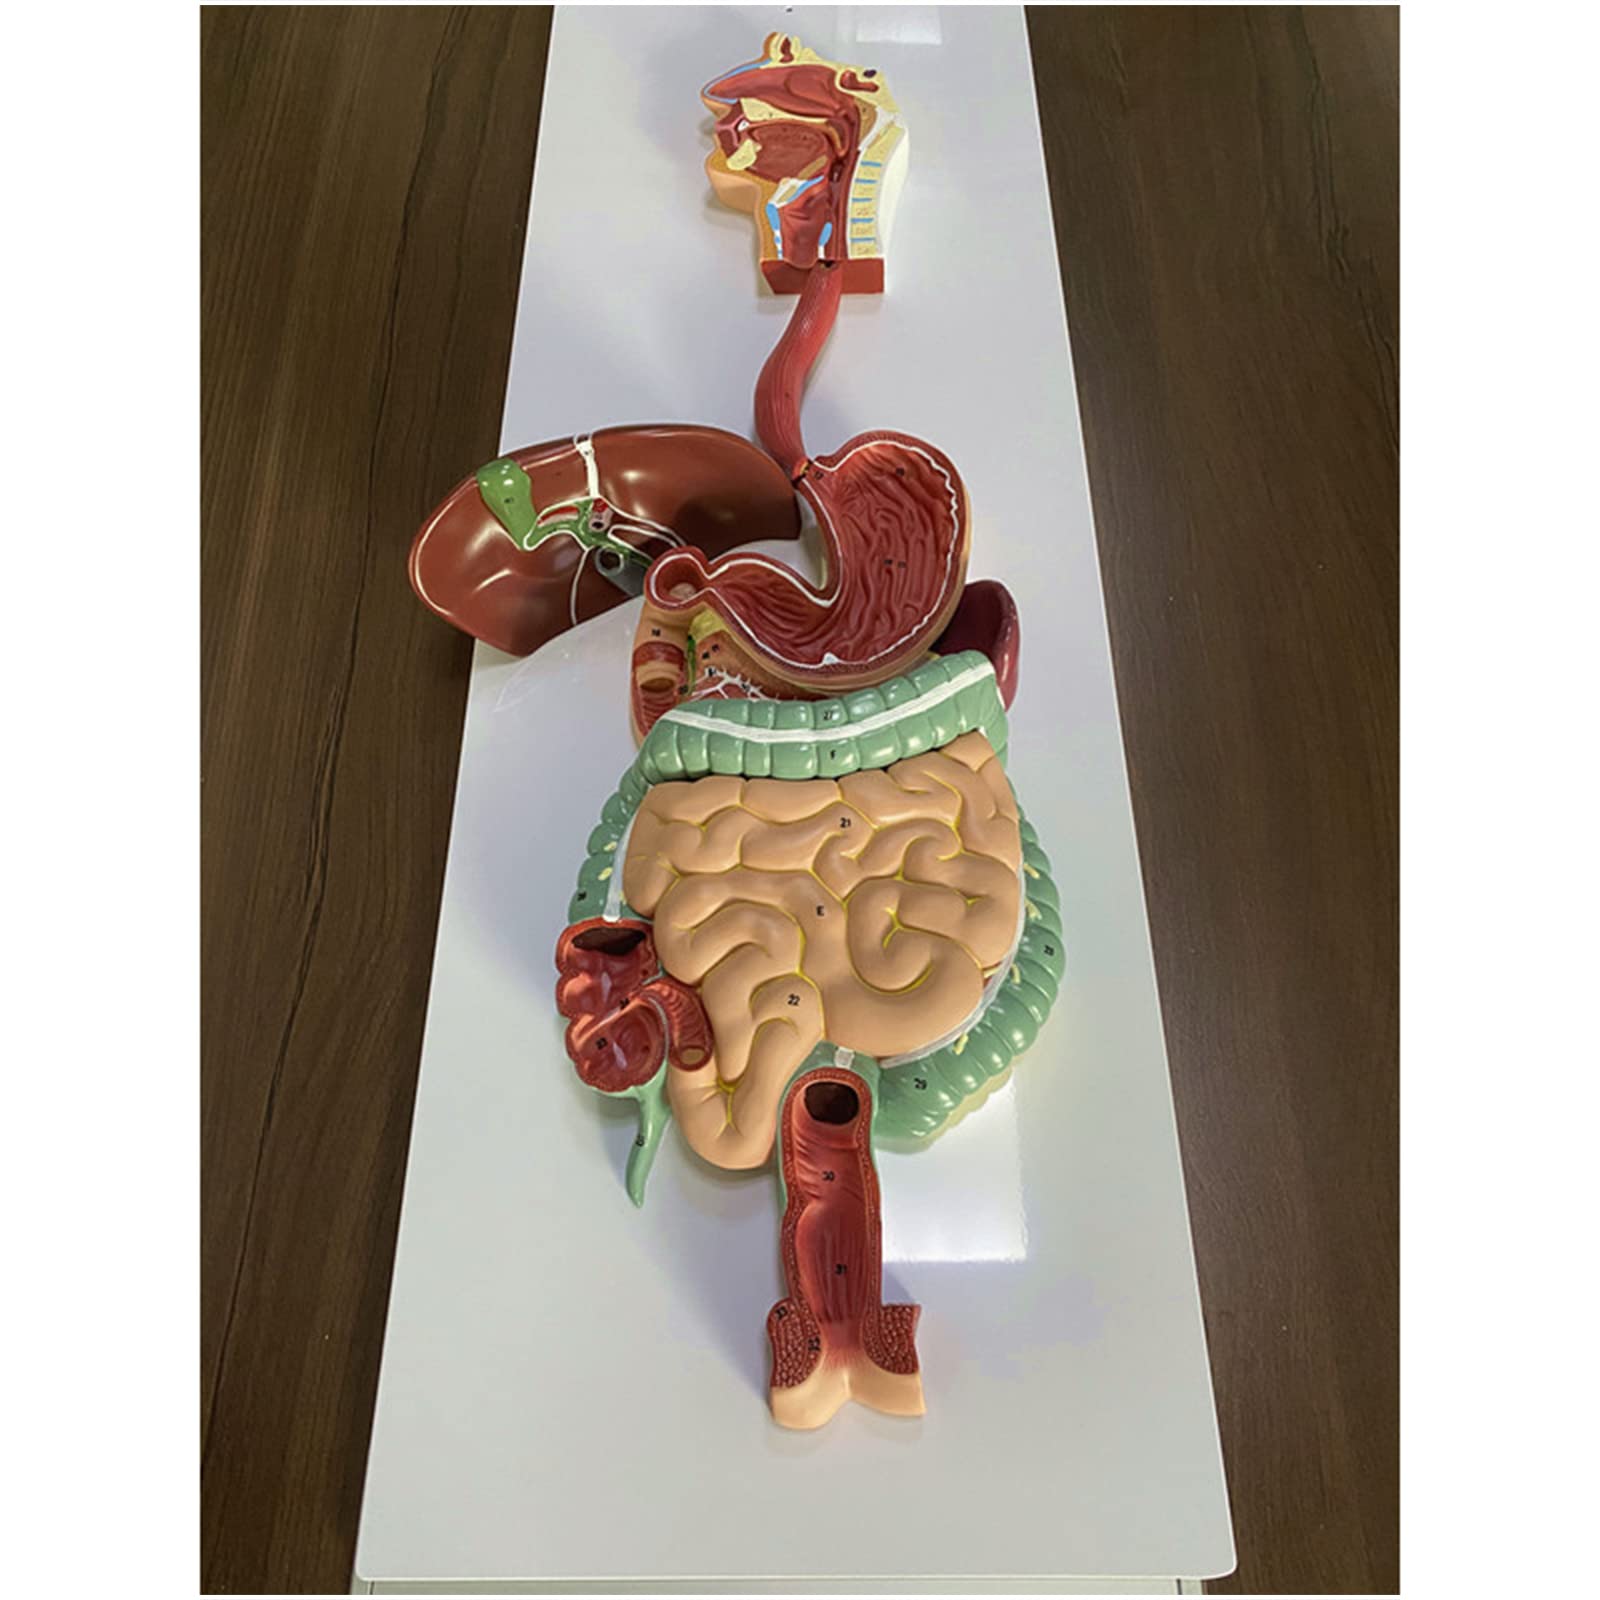

- INTERACTIVE LEARNING EXPERIENCE - Disassemble and explore the digestive system like never before!

The Human Digestive System Model is a life-size, three-dimensional representation of the human digestive tract, designed for educational purposes. It features disassemblable parts for interactive learning and is made from durable, anti-corrosive PVC material, making it an essential tool for anatomy students, educators, and healthcare professionals.